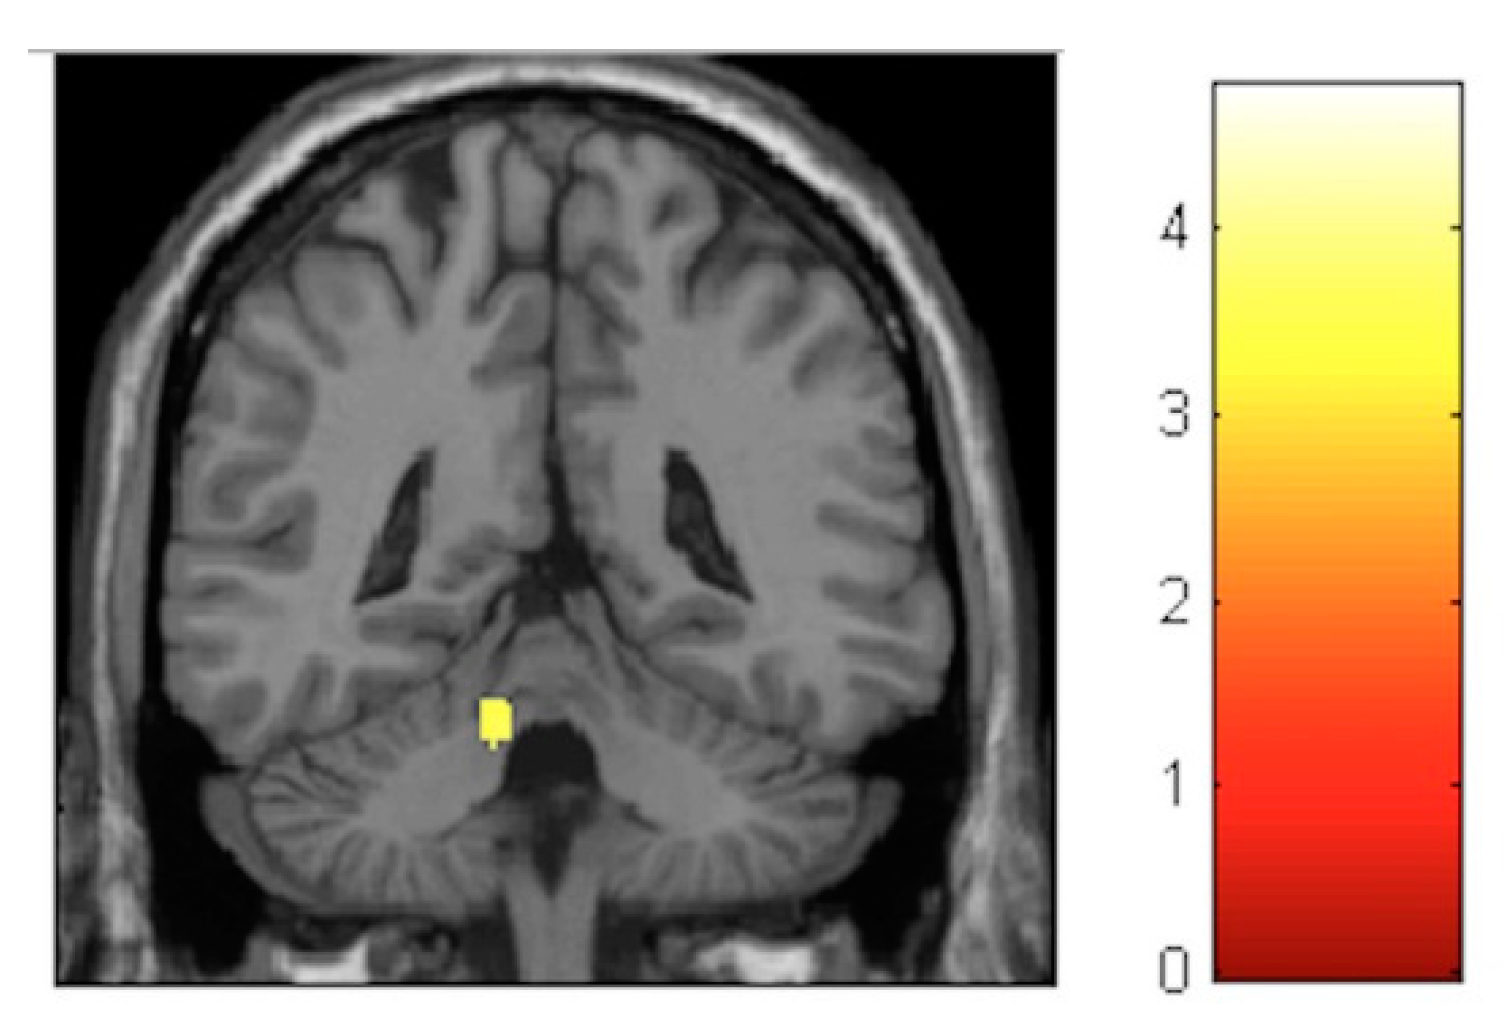

| Effect | Brain Region | Left Hemisphere MNI Coordinates (Cluster Size in Voxels) | T | d | Right Hemisphere MNI Coordinates (Cluster Size in Voxels) | T | d |

|---|---|---|---|---|---|---|---|

| Increment | Paracentral | −9, −32, 59 (1298) | 5.93 | 0.41 | 14, −36, 63 (1589) | 5.47 | 0.40 |

| Increment | Hippocampus | 34, −16, −11.5 (20) | 3.85 | 0.36 | |||

| Decrement | Insula | −32, −10, 12 (60) | 3.91 | 0.36 | 35, −20, 18 (261) | 4.36 | 0.38 |

| Decrement | Putamen | −20, 14, 0 (1879) | 5.45 | 0.40 | 24, 11, 2 (137) | 4.13 | 0.37 |

| Decrement | Cerebellum | −12, −47, −21 (511) | 5.33 | 0.40 | 11, −47, −23 (262) | 4.06 | 0.37 |